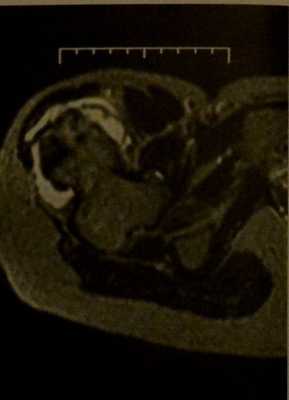

В каких случаях проводят МРТ конечности при остеохондроме кости

- Используется в таких анатомических областях, как кости таза, позвоночник и лопатки, когда перекрывающие их структуры затрудняют визуализацию зоны интереса

- Хрящевое покрытие гиперинтенсивное на Т2-взвешенных изображениях

- Хрящевое покрытие, имеющее толщину более 2 см, - признак, позволяющий заподозрить злокачественный процесс.